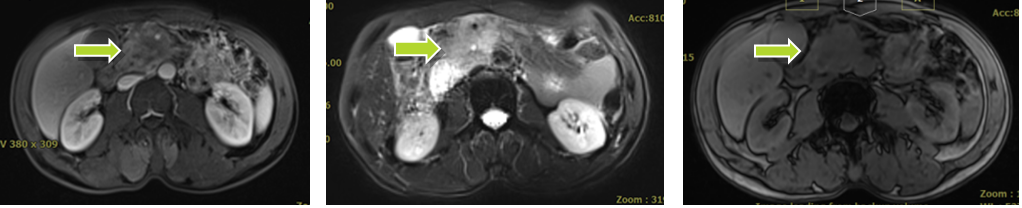

张XX,男,56岁,主诉:间断上腹部胀痛8月,恶心、呕吐10天。入院评估:腹部核磁(2020-12):胰腺钩突部及邻近肠系膜动静脉周围肿块,肠系膜上静脉受侵闭塞,十二指肠水平部压迫及狭窄。临床诊断为:1.胰腺勾突部腺癌;2.十二指肠水平部梗阻;3.重度营养不良;4.胃潴留。

碳离子治疗前患者胰腺病灶

因胰腺病灶压迫十二指肠水平部导致高位消化道肠梗阻,引起胃潴留及进食后呕吐,患者入院后行营养管置管及胃肠减压,保证营养支持充足及胃排空状态前提下,于2020-12-29日开始碳离子治疗,剂量:55.2Gy(RBE),共治疗12次。治疗第7次疼痛明显缓解,治疗期间肿瘤标志物明显下降。治疗后一个月患者完全正常饮食,肿瘤缩小,治疗6个月后肿瘤坏死,活性完全消失。